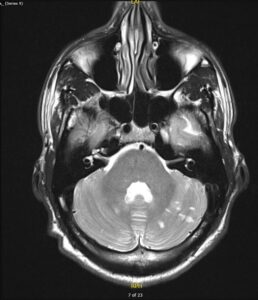

- Brain MRI [Fig 4,5] showed multiple foci of restricted diffusion in bilateral cerebellar hemispheres and the left occipital lobe.